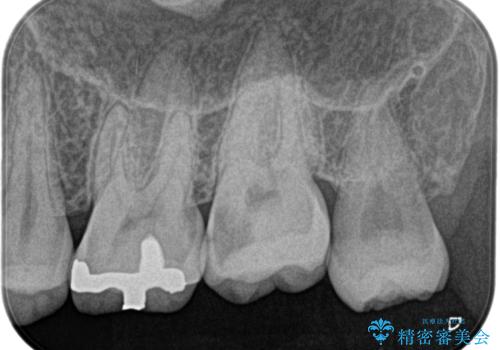

【精密根管治療】奥歯がズキズキ痛い。

- 奥歯がズキズキ痛いことを主訴に来院されました。

治療にて歯髄は保存できないと判断したため、根管治療を行いセラミッククラウンにて修復しております。

自発痛の既往がある場合は、抜髄の適応となることが多いです。